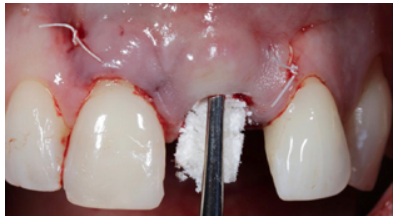

Different protocols have also been established for the management of the anterosuperior aesthetic sector, in addition to performing the immediate implant and provisional crown, including placing material between the OII and the buccal cortical to minimise possible collapse and the management of peri-implant soft tissue8-11.

Conclusions: Rehabilitation on implants in situations of tooth loss in the aesthetic anterior sector, especially in young patients, requires a multidisciplinary treatment plan to extract the tooth and insert an OII in the correct 3-dimensional position. Various aspects need to be taken into account for this, particularly the residual remaining bone, the position of the gingival margin and preservation and conditioning of the peri-implant hard and soft tissues by means of grafts and proper handling of provisional prosthesis, until an ideal emergence profile and gingival contour is achieved before the final crown.